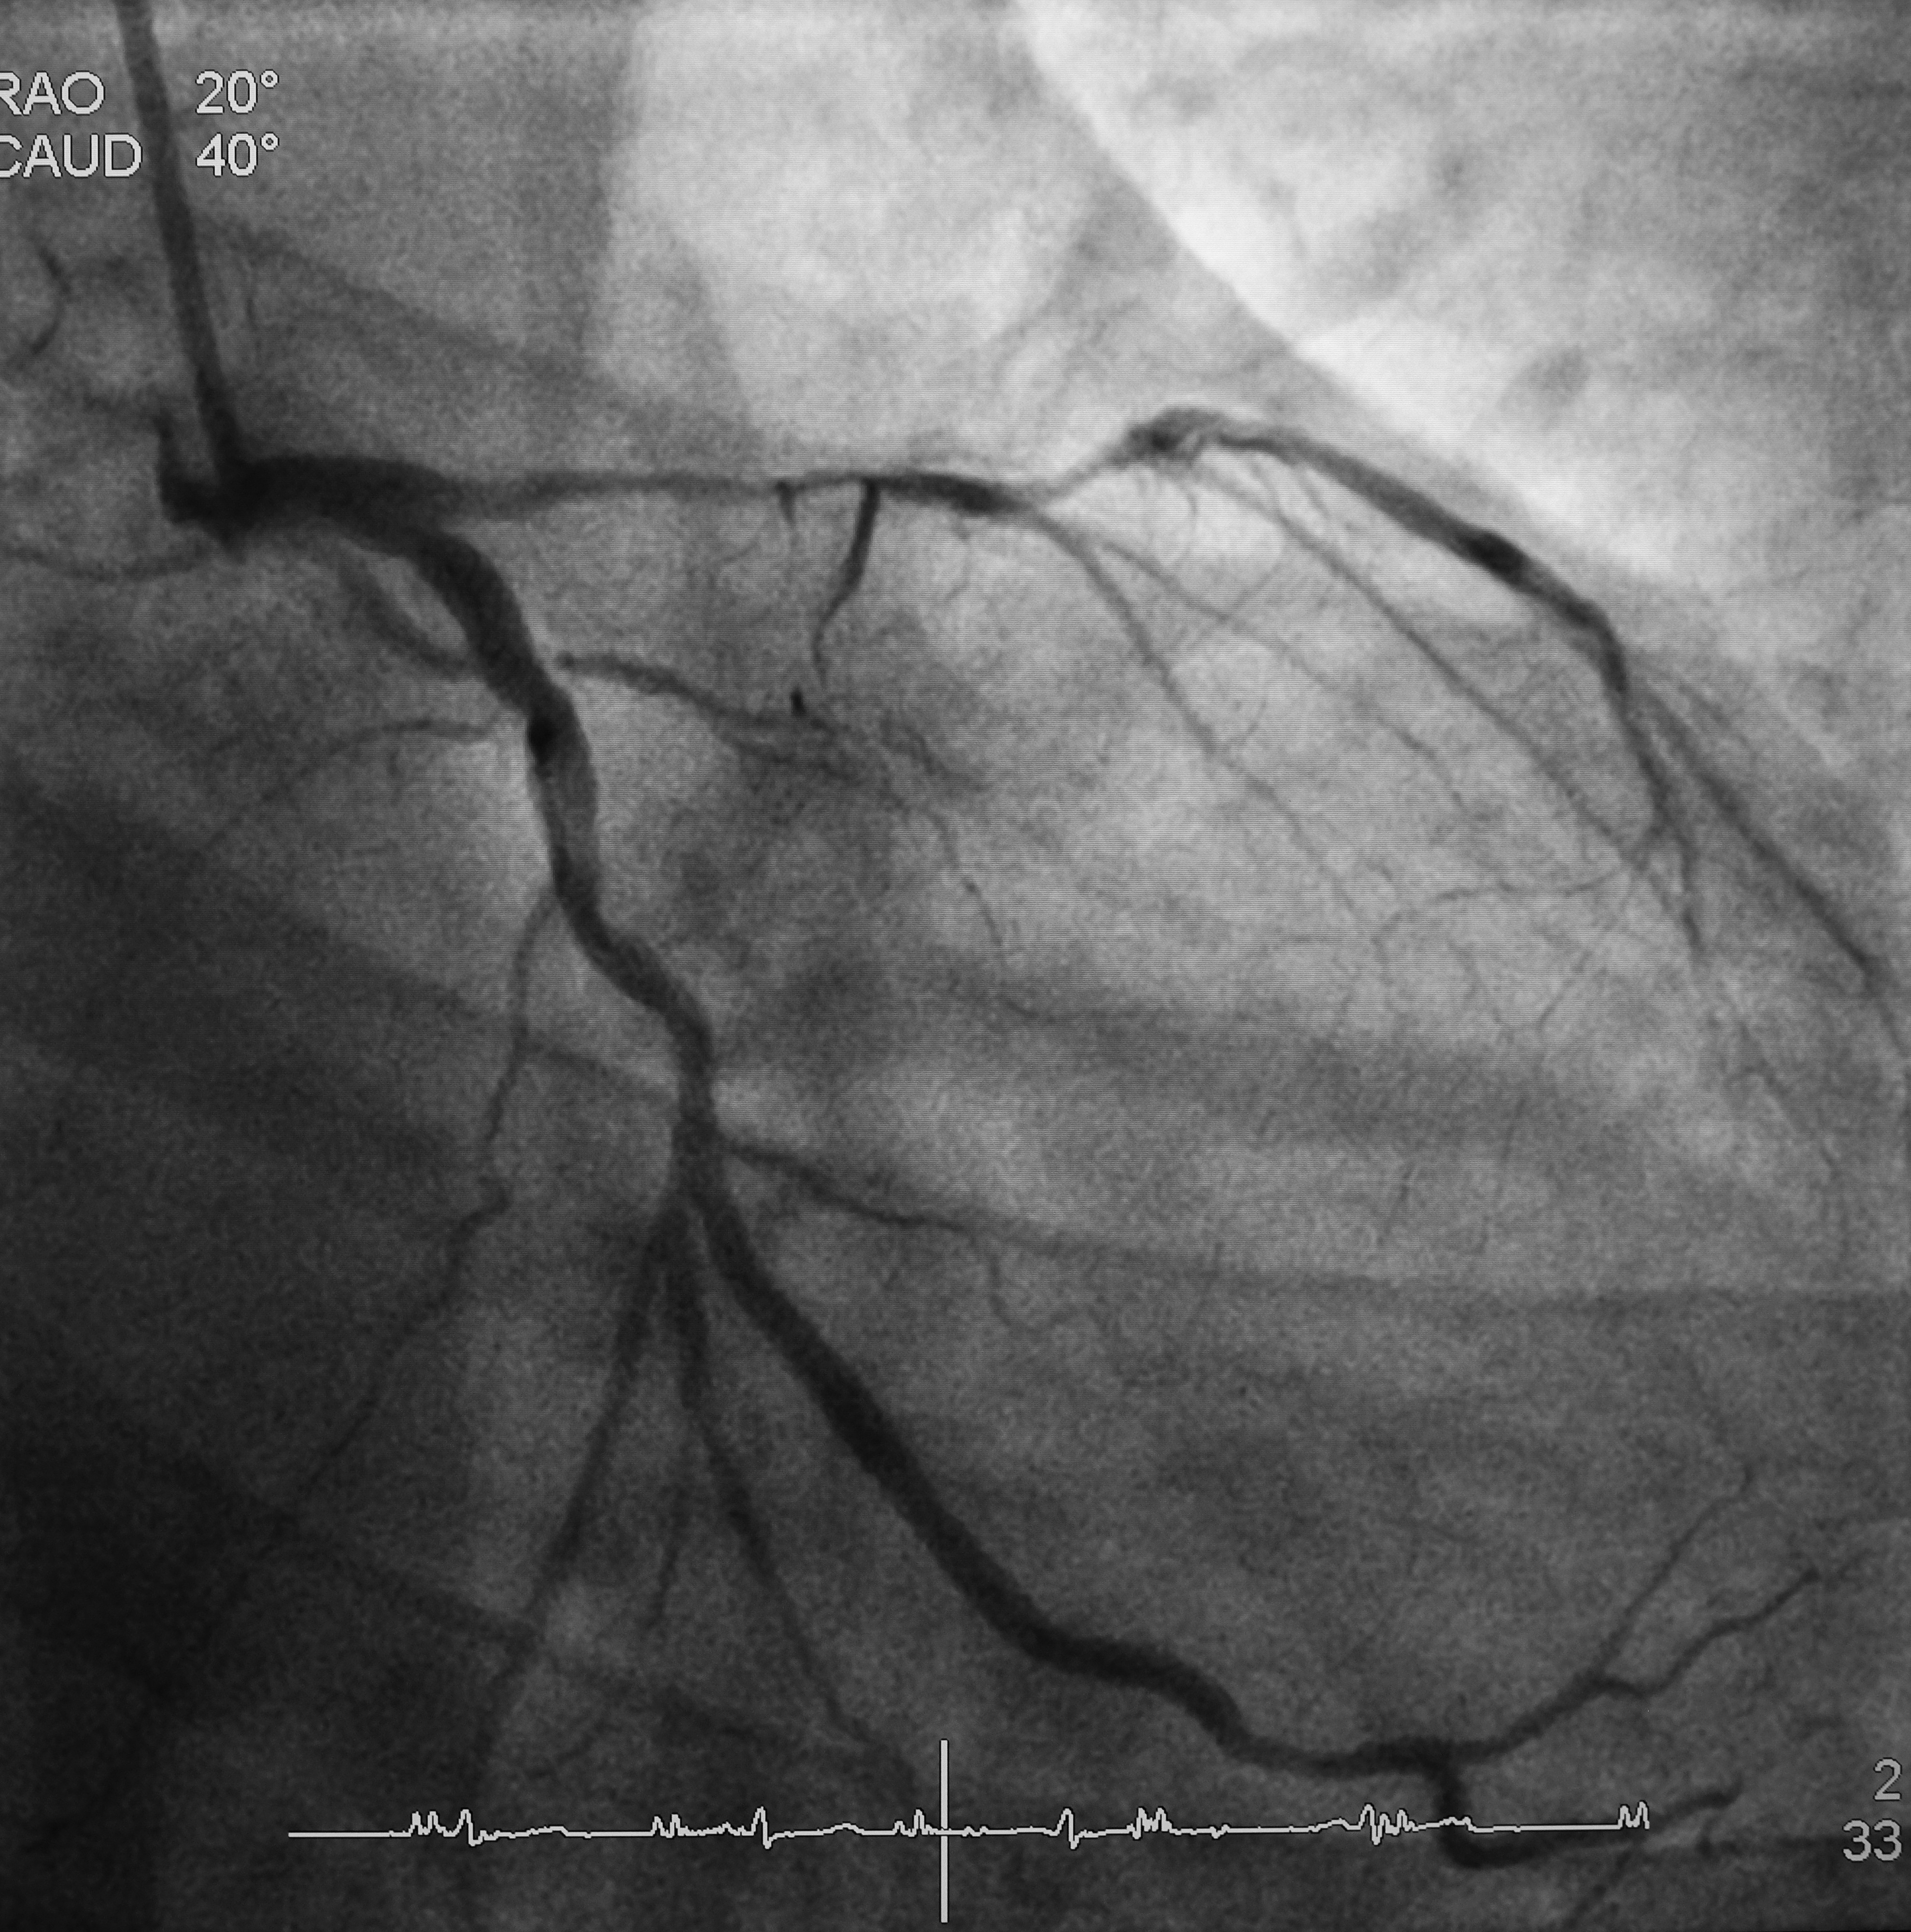

We’re building ultrasound catheters for rapid clot disruption and

microvascular protection during PCI.

SonoRobotics develops catheter-based ultrasound technology for thrombus disruption and microvascular protection in PCI workflows.